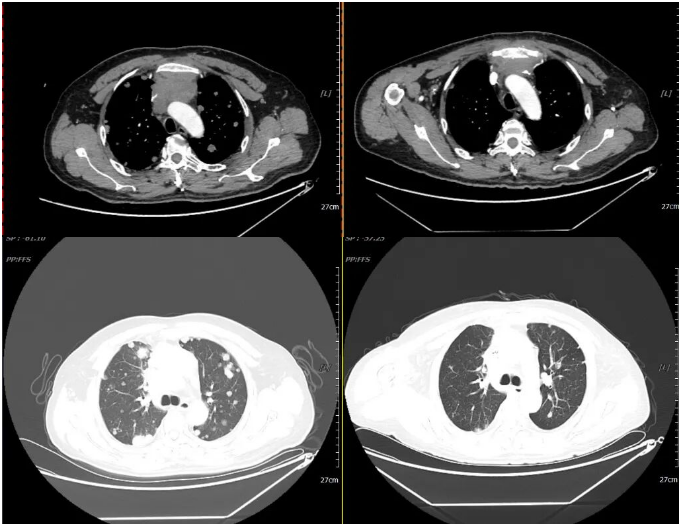

2021-07-06 2021-12-11

2021-03-05 2021-12-10

2021年12月11日疗效评价:PD(两肺及胸膜结节明显增多、增大;纵隔前间隙、纵隔内及两肺门转移淋巴结(现约4.7×3.5cm)较前增多、增大,上腔静脉、左头臂静脉受累狭窄;双侧小脑半球、大脑半球转移(约2.1×1.7cm)新发。

2021-12-11 2022-03-23

2周期治疗后 疗效评估:PR(部分缓解)